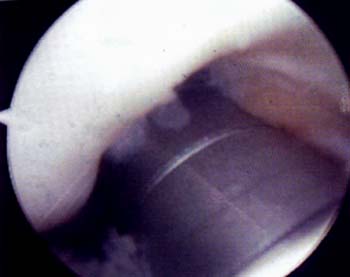

Retensado Interno

Se realizo el retensado artrosc6pico de afuera adentro sobre el retinkulo medial junto a la membrana sinovial. Cuatro o cinco puntos son suficientes y se reali cruentado capsulo-sinovial interno con el fin provocar una cicatriz fibrosa que colabore con la plastica luego de la reabsorcion del material de sutura. La plastica se realiza desde el límite del vasto interno hasta las ultimas fibras distales del retinkulo. El retensado interno se realiza por medio de una tecnica simple y con instrumental de sutura artroscopica. Por una aguja pasahilo se introduce la sutura y con otra aguja pescahilo se toma la misma por dentro efectuando una plicatura trans-sinovial. La magnitud de la plicatura estard determinada por la tension necesaria para el correcto centrado de la patela. Utilizamos sutura de polidioxanona y se dejan reparados los puntos por fuera hasta haber finalizado la liberacion externa, en que se fijan los puntos internos y se evaltia el centrado patelar. Una vez finalizado el procedimiento se realiza una confirmacion dinamica artroscopica del centrado rotuliano en flexion y extension, la relacion entre la pate-la y los condilos femorales y la orientacion de las carillas articulares rotulianas. Grafico I , Fotos 1 y 2.

Foto 1: Vista artroscopica de la Monica de retensa interno.